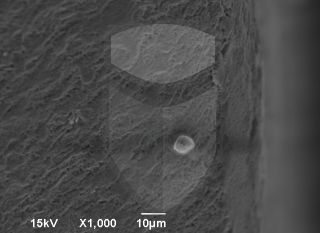

Implante 5 estrelas. Boa usinagem, algumas poucas rebarbas e ótima limpeza.

Topografia/rugosidade:

Marca e tipo de microscópio:

Jeol JSM 6390 Lv